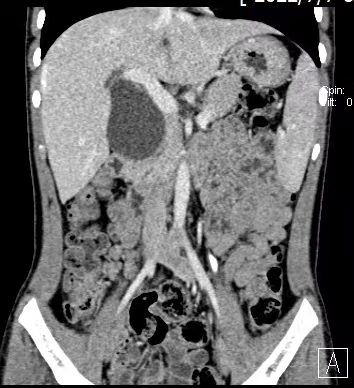

先天性膽總管囊腫是一種較少見但危害嚴重的膽道先天畸形,可能導(dǎo)致膽汁淤積、反復(fù)膽管炎、胰腺炎,并有遠期癌變風(fēng)險。根治性切除囊腫并重建膽道是唯一有效的治療方法。然而,幼兒腹腔空間小、組織器官嬌嫩、血管膽管纖細,手術(shù)操作猶如“精雕細琢”,對主刀醫(yī)生的技術(shù)、經(jīng)驗以及整個麻醉、護理團隊的配合都提出了極高要求。

術(shù)中,手術(shù)團隊在放大數(shù)倍的高清視野下,精細分離、完整切除了巨大的膽總管囊腫,并成功實施了“肝總管-空腸Roux-en-Y吻合術(shù)”,在徹底去除病灶的同時,為患兒建立了通暢、符合生理的膽汁引流通道。整個手術(shù)過程如行云流水,出血量極少,最大程度保護了周圍稚嫩的組織結(jié)構(gòu)。